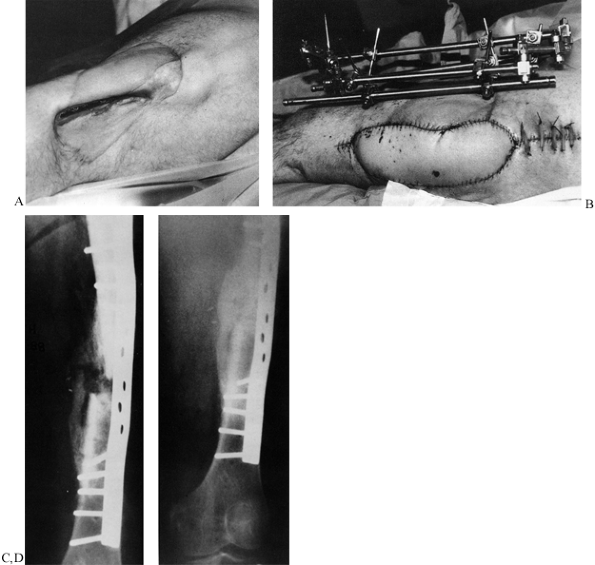

Figure 30.6. Wave plate: A: A 27-year-old man presented with an infected nonunion of 13 months duration. B:

Debridement was performed with application of an external fixator, using a latissimus free flap to cover the defect at a subsequent debridement 2 weeks later. C: Three weeks after soft-tissue coverage, the patient underwent stabilization using a 16-hole broad dynamic compression plate with wave configuration augmented with iliac crest bone graft. D: At 7 months, the fracture had consolidated, and the patient was fully weight bearing without pain. (From Cove JA, Lhowe DW, Jupiter JB, Siliski JM. The Management of Femoral Diaphyseal Nonunions. J Orthop Trauma 1997;11:513, with permission.) |